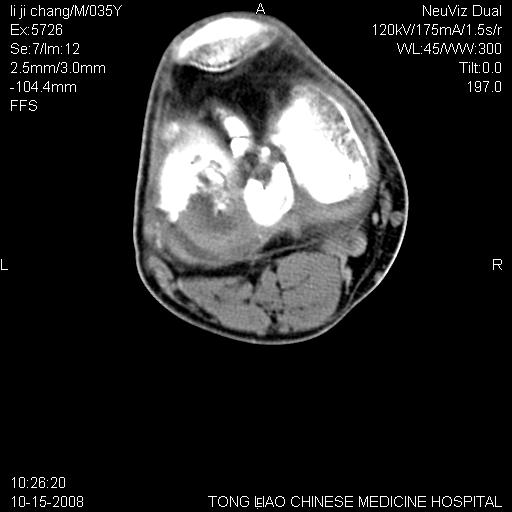

男,35岁,骨科诊断骨性关节炎。继往使用过激素,现股骨头坏死。膝关节病变,请会诊

一元论-----亦考虑为坏死

支持考虑无菌坏死

支持无菌坏死伴退行性骨关节病.

剥脱性骨软骨炎:是一种关节下软骨及软骨下骨缺血性坏死。

支持 无菌性坏死伴退行性骨关节病。

支持无菌坏死伴退行性骨关节病